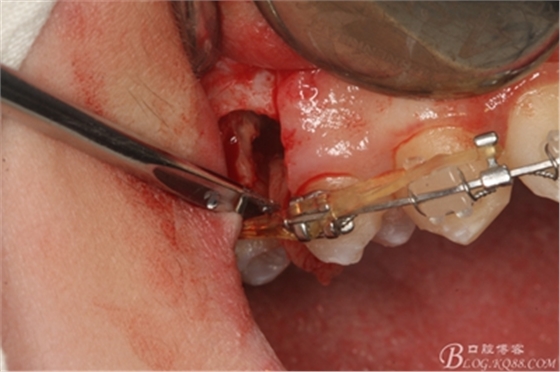

圖11.仔細考慮之后,在14頰側(cè)做垂直切口,切口長度僅達膜齦聯(lián)合處,做小切口。

圖12. 做垂直切口+齦溝內(nèi)切口,形成角形瓣,暴露出15根面。